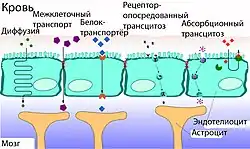

Транспорт веществ через ГЭБ

Гематоэнцефалический барьер не только задерживает и не пропускает целый ряд веществ из крови в вещество мозга, но и выполняет противоположную функцию — транспортирует необходимые для метаболизма ткани мозга вещества. Гидрофобные вещества и пептиды проникают в мозг либо с помощью специальных транспортных систем, либо через каналы клеточной мембраны. Для большинства других веществ возможна пассивная диффузия[6][36].

Межклеточный транспорт

В капиллярах периферических органов и тканей транспорт веществ осуществляется в основном через фенестра́ции сосудистой стенки и межклеточные промежутки. В норме между клетками эндотелия сосудов мозга такие промежутки отсутствуют. В связи с этим питательные вещества проникает в мозг лишь через клеточную мембрану[118]. Вода, глицерин и мочевина являются примерами тех небольших поляризованных молекул, которые могут свободно диффундировать через плотные контакты между эндотелиальными клетками ГЭБ[119].

Свободная диффузия

Самой простой формой транспорта через ГЭБ является свободная (или пассивная) диффузия. Она может осуществляться как через клеточные мембраны эндотелиоцитов, так и через плотные межклеточные контакты. Для диффузии веществ движущей силой является разница концентраций. Диффузия веществ пропорциональна градиенту концентраций в кровеносном русле и ткани мозга. Для неё не требуется затрат клеточной энергии[120].

Липофи́льные структурные элементы клеточной мембраны, а также плотные межклеточные контакты снижают количество веществ, которые могут свободно диффундировать через ГЭБ. Проницаемость ГЭБ напрямую зависит от липофильности каждого конкретного вещества[121].

Проницаемость ГЭБ также зависит от молярной массы вещества. Молекулы с массой более 500 г/моль не могут диффундировать через ГЭБ. В то же время ГЭБ не является механическим барьером, который свободно пропускает молекулы меньшего размера и не пропускает большего. Процесс клеточной диффузии является динамическим, при этом он легче для веществ с молярной массой 200 г/моль, чем для веществ с 450 г/моль[41][122]. Чем липофильнее и меньше вещество, тем легче оно диффундирует через клеточную мембрану[6].

Облегчённая диффузия

Особой формой диффузии через клеточную мембрану является облегчённая диффузия. Целый ряд необходимых для мозга веществ, как например, глюкоза и многие аминокислоты, полярны и слишком велики для непосредственной диффузии через клеточную мембрану. Для них на поверхности клеточных мембран эндотелиоцитов располагаются специальные транспортные системы. Например, для глюкозы и аскорбиновой кислоты (витамина С)[139] это GLUT-1-транспортёр. Их количество на поверхности обращённой в полость сосуда в 4 раза больше, чем на обращённой к мозгу.

Кроме транспортёров глюкозы на поверхности эндотелия располагаются множество белковых молекул выполняющих подобную функцию для других веществ. Так например MCT-1 и MCT-2 ответственны за перенос лактата, пирувата, мевалоновой кислоты, бутиратов и ацетатов. SLC7 транспортирует аргинин, лизин и орнитин. В геноме мыши выявлено 307 генов отвечающих за синтез SLC-белков, ответственных за облегчённую диффузию через клеточную мембрану различных веществ[140].

Транспортёры могут осуществлять перенос веществ в одном либо двух направлениях[141]. В отличие от активного транспорта облегчённая диффузия направлена в сторону пространства (внутри- или внеклеточного) с меньшей концентрацией вещества и не требует затрат клеточной энергии.

Активный транспорт

В отличие от пассивного транспорта, не требующего затрат энергии, активный заключается в переносе веществ в пространство с большей концентрацией вещества и требует больших затрат клеточной энергии, получаемой при распаде молекул АТФ[118]. При активном транспорте веществ из кровеносного русла в ткань мозга говорят о притоке вещества (англ. influx), в обратном направлении — об оттоке (англ. efflux).

Везикулярный транспорт

Рецептор-опосредованный трансцитоз

С помощью рецептор-опосредованного трансцито́за происходит перенос больших молекул. На обращённой в просвет сосуда поверхности клетки расположены специальные рецепторы для опознавания и связывания определённых веществ[23]. После контакта рецептора с веществом-мишенью происходит их связывание, участок мембраны инвагинируется в полость клетки и образуется внутриклеточный пузырёк — везикула. Затем она перемещается к обращённой к нервной ткани поверхности эндотелиальной клетки, сливается с ней и высвобождает связанные вещества. Таким образом во внеклеточное пространство мозга переносятся состоящий из 679 аминокислот белок трансферрин массой 75,2 кДа[162], липопротеины низкой плотности из которых образуется холестерин[130][163], инсулин[164] и другие пептидные гормоны[23].

Абсорбцио-опосредованный трансцитоз

Одним из подвидов везикулярного транспорта является абсорбцио-опосредованный трансцитоз. Отмечается «прилипание» ряда положительно заряженных веществ (катионов) к отрицательно заряженной клеточной мембране с последующем образованием везикулярного пузырька и его переносом к противоположной поверхности клетки. Данный вид транспорта также называется катионным. Он проходит относительно быстрее рецептор-опосредованного трансцитоза[165][166][167][168].